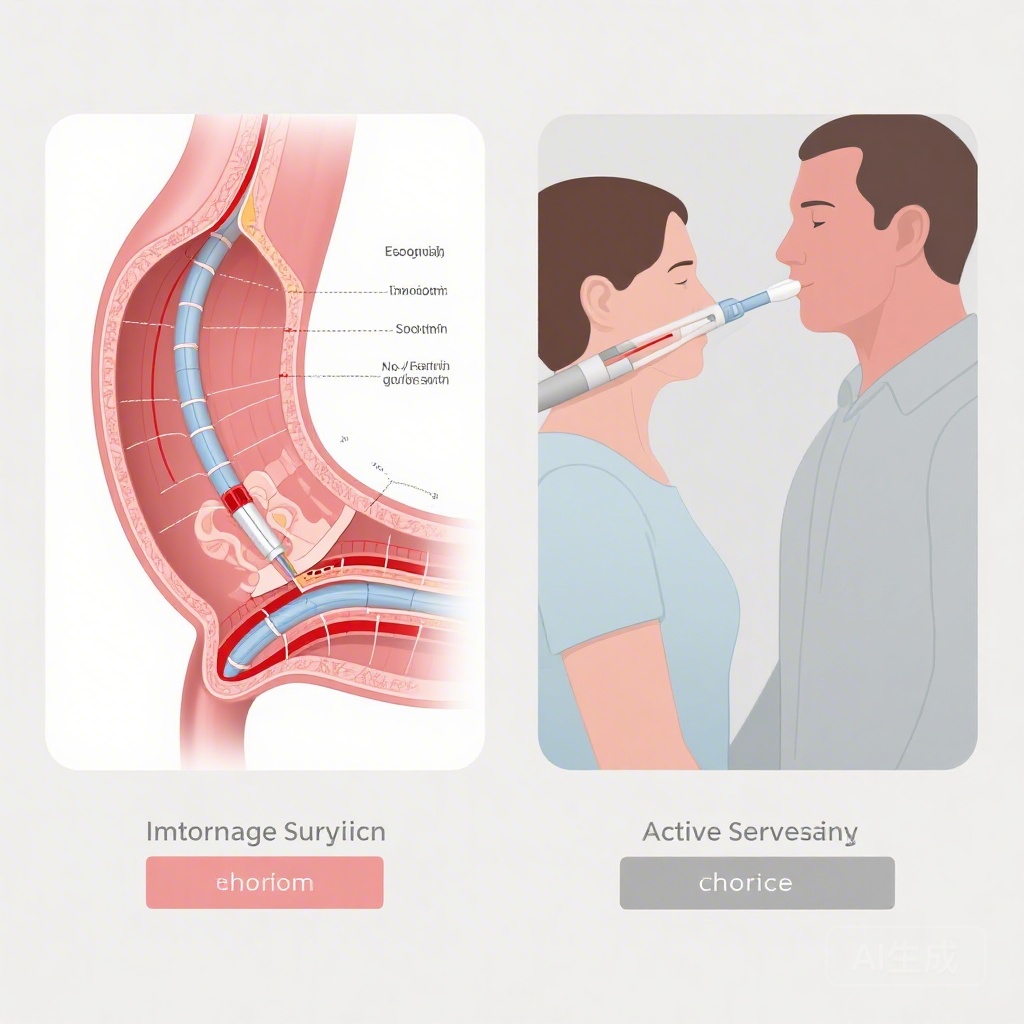

Hiệu suất được giải phóng: Nhóm Tim Trực tuyến Thời gian Thật Chuyển đổi Quản lý CAD Phức tạp trong Thử nghiệm EHEART

Thử nghiệm EHEART tiết lộ rằng các cuộc thảo luận trực tuyến thời gian thực của nhóm tim trong quá trình chụp mạch vành đáng kể cải thiện hiệu quả lâm sàng và giảm chi phí cho bệnh nhân CAD phức tạp, đồng thời duy trì kết quả an toàn 1 năm không thua kém so với các cuộc họp đa ngành truyền thống.